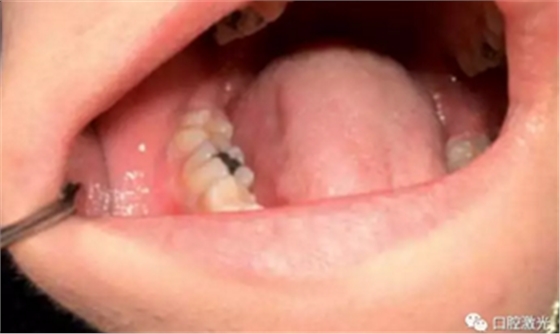

术后1周、4周、6个月以及1年对患者进行追踪观察。1周复诊时,重点了解疼痛、出血以及水肿的情况。其结果为没有出现上述情况。所有的患者都可以术后立即恢复正常的生活、学习、工作活动。并且,术后没有使用止疼药和消炎药。在4周时,评估伤口的愈合情况,所有的患者都恢复很好,没有出现并发症现象。在6个月至1年期间,没有出现任何形式的复发。因此,患者对激光手术的效果评价十分高。

通过口腔激光对龈瘤进行手术切除有着众多优势。其中,由于对血红蛋白的吸收率很高,半导体激光有着优秀的凝血效果。不但术中出血量大大减少,同时给医生提供了一个良好的手术视野。术后的优势也是显而易见的,伤口愈合的速度更快,没有疼痛和水肿的发生。大大缩短的手术时间,减少了患者对手术治疗的恐惧心理。因此对于患者和医生来说都十分受益于口腔激光。